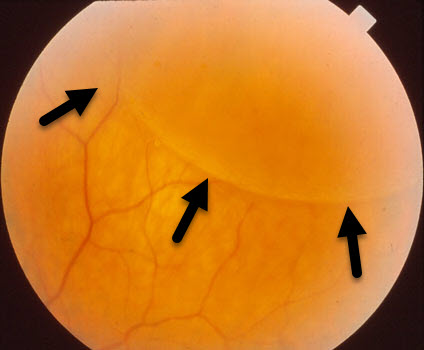

The retina lines the inside of the eye like wallpaper. It has multiple layers that are normally stuck together. Degenerative retinoschisis is an age-related disorder where these layers split.

Virtually all patients with degenerative retinoschisis are completely asymptomatic. The retinal splitting, which may be in one or both eyes, is detected by your eye doctor during a dilated retinal examination as a smooth solid retinal elevation.

Almost all patients with degenerative retinoschisis need no treatment since the retinal splitting does not usually progress. Rarely patients can develop holes within the split tissue that can mimic or cause a retinal detachment. Patients are usually examined every 6 to 12 months. New flashes, floaters or painless side vision loss are symptoms of a retinal detachment and need to be examined immediately.